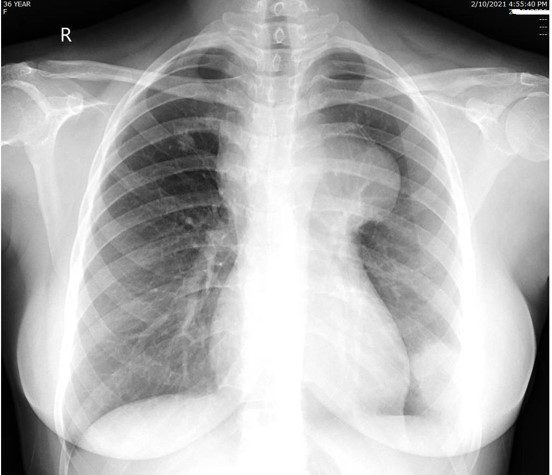

FRCR cases are exam-style radiology cases that simulate the FRCR 2B exam experience. Unlike textbooks, case-based practice allows you to apply knowledge in realistic scenarios, interpreting imaging, forming differential diagnoses, and practising structured reporting.

Understand the FRCR 2B exam format, including short cases & oral exams. Learn what candidates are assessed on & how to prepare effectively.

Preparing for the FRCR 2B exam requires more than reading textbooks or reviewing notes. Success depends on developing structured reporting skills, improving pattern recognition, and becoming confident in exam-style case interpretation.